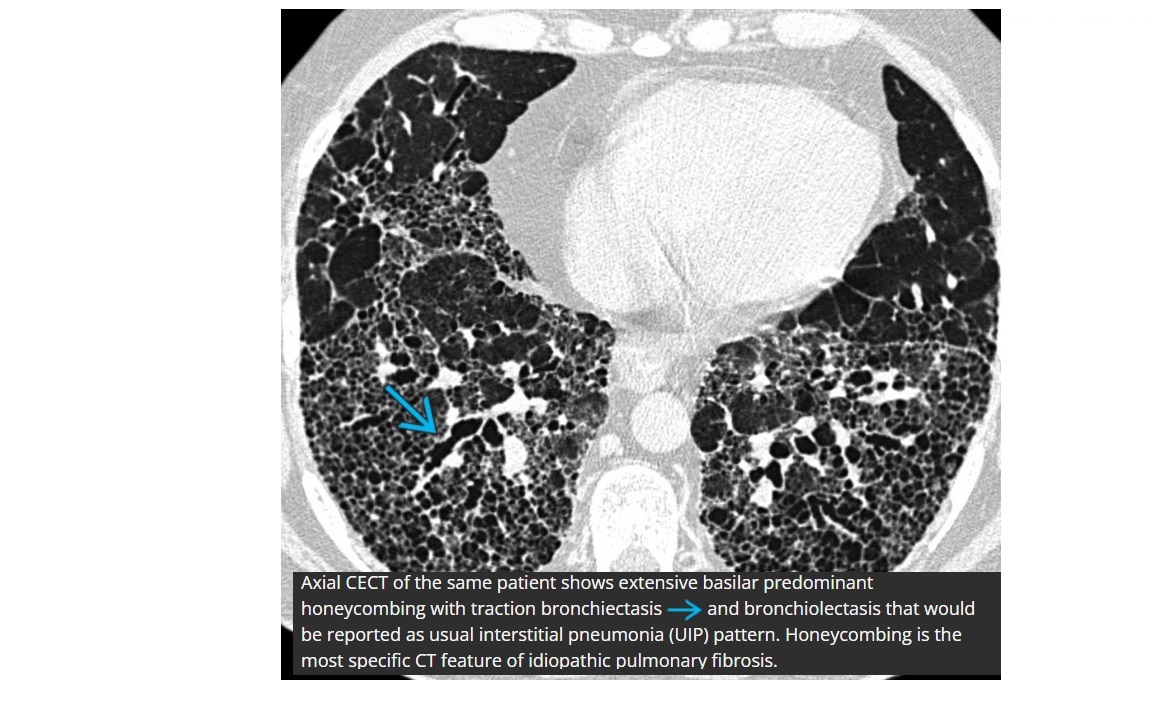

UIP

CXR

Reticular or reticulonodular opacities

Subpleural/peripheral; mid and lower lung zones

Macrocystic Honeycombing (strongest predictor)

Basilar predominant

Traction bronchiectasis

Subpleural reticulations

smoking association

Causes

- connective tissue disease such as RA

- asbestosis

- Drugs (amidorane, nitrofurantoin, methotrexate)

- IPF (diagnosis of exclusion)